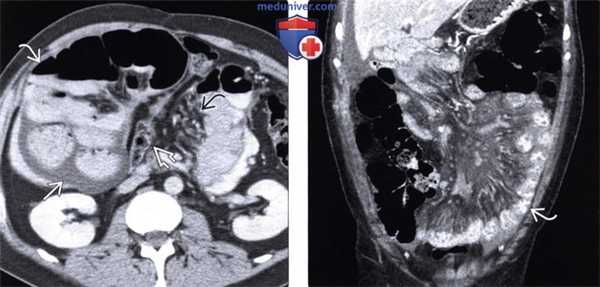

(Слева) На аксиальной КТ определяется правосторонняя парадуоденальная грыжа, которая стала причиной обструкции тонкой кишки. Обратите внимание на U-образную конфигурацию кишечной петли в грыжевом мешке.

(Справа) На корональной КТ с контрастным усилением определяется левосторонняя парадуоденальная грыжа, выглядящая «инкапсулированной» (типичное проявление). Обратите внимание на полнокровные брыжеечные сосуды, идущие прямо в грыжевой мешок.